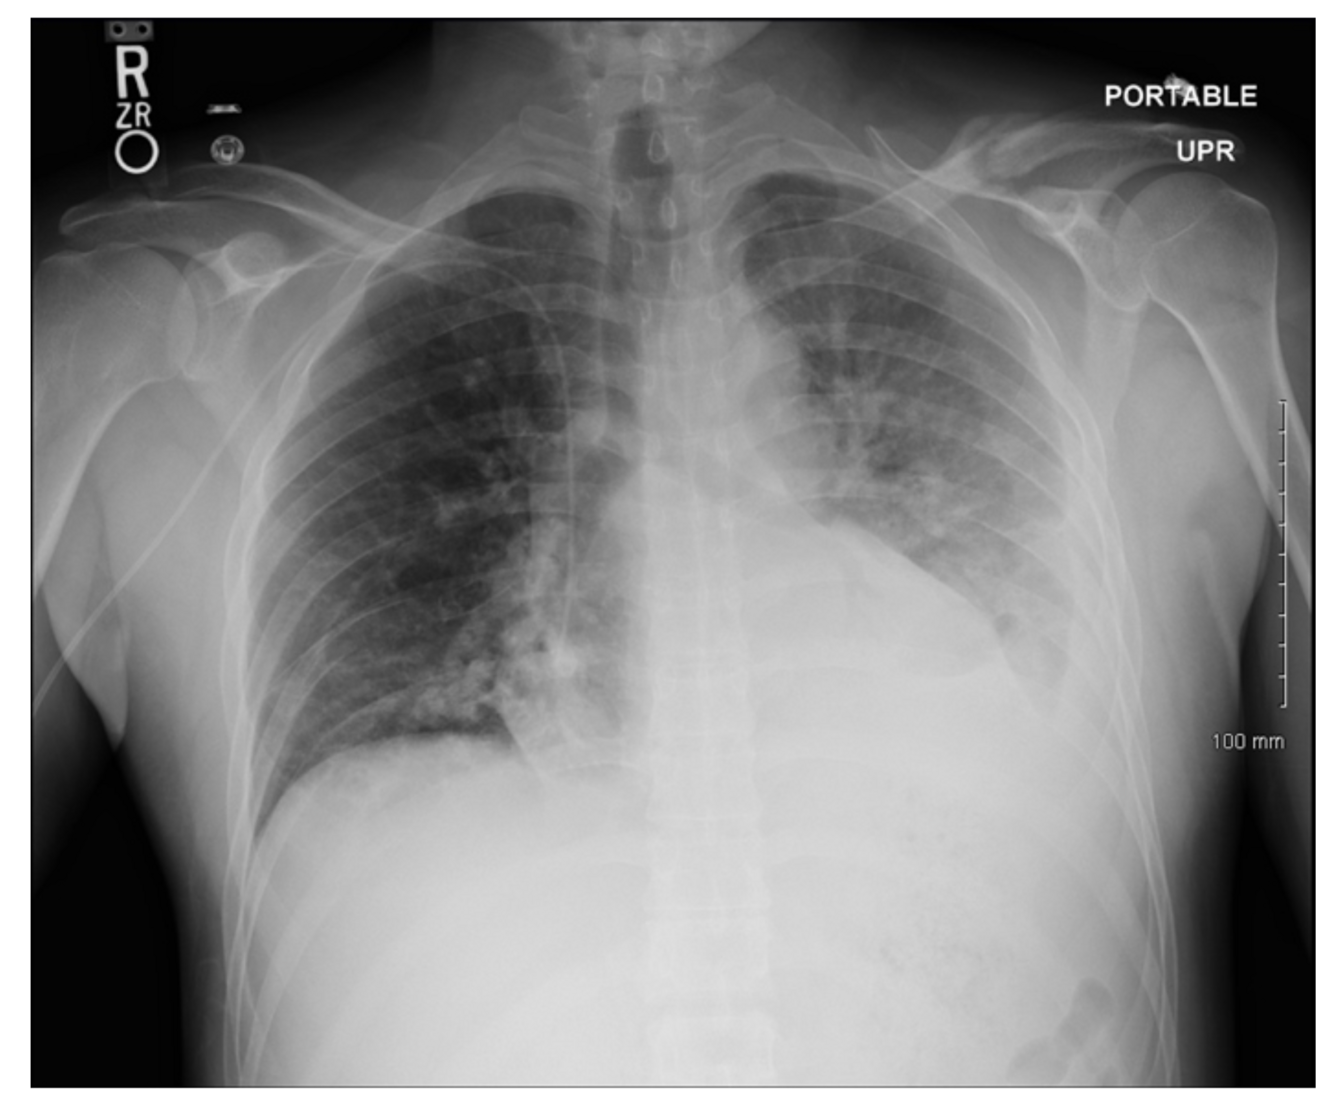

What is the first-line imaging study for pleural effusion?

Chest X-ray (CXR), which shows blunting of the costophrenic angles.

What is characteristic of pleural effusions secondary to heart failure?

Bilateral, perihilar patchy infiltrates.